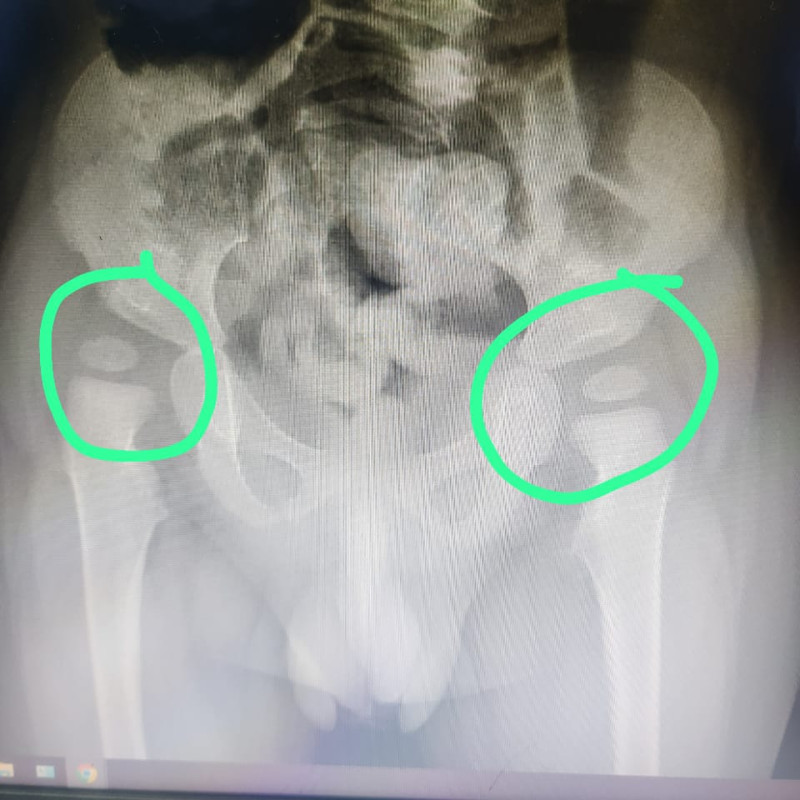

Saat usianya 8 bulan, Ryuga sudah didiagnosa kerusakan otak yang membuatnya tidak bisa mengontrol gerakan tubuh dan ototnya (Cerebral Palsy), serta didiagnosa infeksi pada bagian belakang tenggorokannya (Faringo).

Tubuh anakku menjadi kaku dan ia sulit bernapas. Di usianya yang sekarang, ia hanya bisa terbaring lemah. Bahkan sekedar untuk tertawa saja belum bisa. Setiap hari aku menanti keajaiban, berharap suatu hari ia bisa tertawa lepas dan bahagia.

Saat usianya 8 bulan, Ryuga sudah didiagnosa kerusakan otak yang membuatnya tidak bisa mengontrol gerakan tubuh dan ototnya (Cerebral Palsy), serta didiagnosa infeksi pada bagian belakang tenggorokannya (Faringo).

Tubuh anakku menjadi kaku dan ia sulit bernapas. Di usianya yang sekarang, ia hanya bisa terbaring lemah. Bahkan sekedar untuk tertawa saja belum bisa. Setiap hari aku menanti keajaiban, berharap suatu hari ia bisa tertawa lepas dan bahagia.